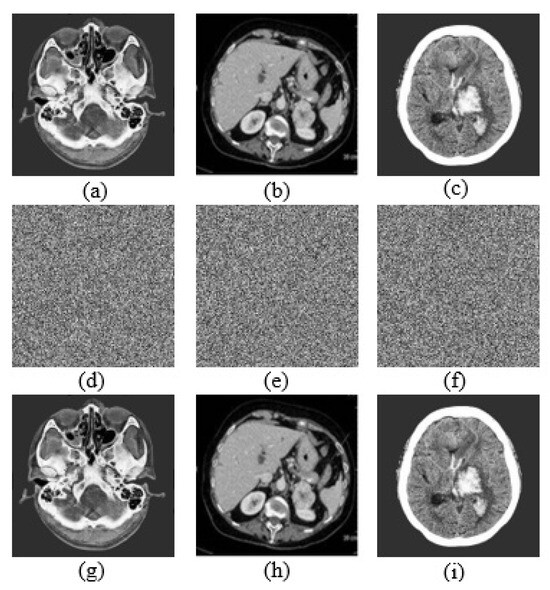

24 pages, 26851 KB

Article

A Novel Dual Color Image Watermarking Algorithm Using Walsh–Hadamard Transform with Difference-Based Embedding Positions

by Yutong Jiang, Shuyuan Shen, Songsen Yu, Yining Luo, Zhaochuang Lao, Hongrui Wei, Jing Wu and Zhong Zhuang

Symmetry 2026, 18(1), 65; https://doi.org/10.3390/sym18010065 - 30 Dec 2025

Image watermarking is an essential technique for protecting the copyright of digital images. This paper proposes a novel color image watermarking algorithm based on the Walsh–Hadamard Transform (WHT). By analyzing the differences among WHT coefficients, an asymmetric embedding position selection strategy is designed [...] Read more.

Image watermarking is an essential technique for protecting the copyright of digital images. This paper proposes a novel color image watermarking algorithm based on the Walsh–Hadamard Transform (WHT). By analyzing the differences among WHT coefficients, an asymmetric embedding position selection strategy is designed to enhance the robustness of the algorithm. Specifically, the color image is first separated into red (R), green (G), and blue (B) channels, each of which is divided into non-overlapping 4 × 4 blocks. Then, suitable embedding regions are selected based on the entropy of each block. Finally, the optimal embedding positions are determined by comparing the differences between WHT coefficient pairs. To ensure watermark security, the watermark is encrypted using Logistic chaotic map prior to embedding. During the extraction phase, the watermark is recovered using the chaotic key and the pre-stored embedding position information. Extensive simulation experiments are conducted to evaluate the effectiveness of the proposed algorithm. The comparative results demonstrate that the proposed method maintains high imperceptibility while exhibiting superior robustness against various attacks, outperforming existing state-of-the-art approaches in overall performance. Full article